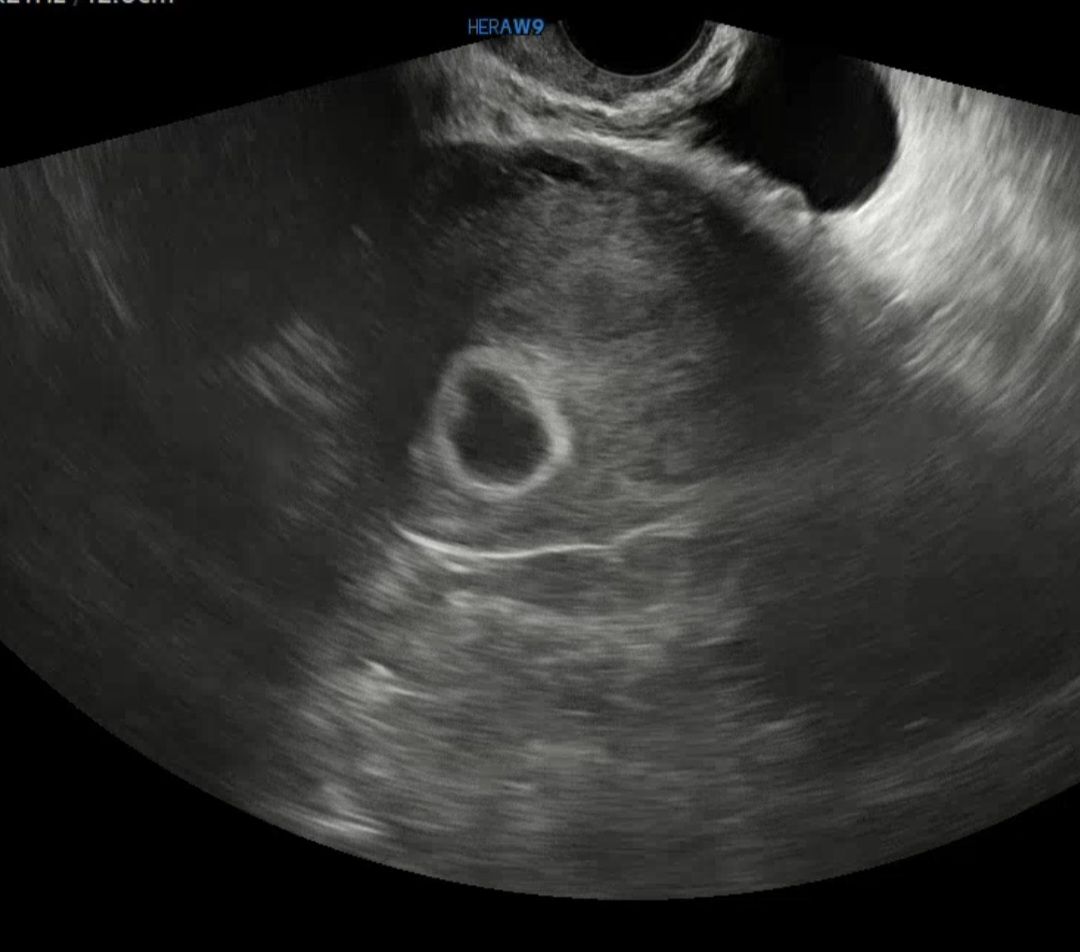

난황..

막생 5월6일이고 오늘 초음파 확인 시 난황 안보인다고 1주후에 다시 보자고 하셨어요.. 아기집 보이고 자리도 잘 잡았다고 하는데ㄷㅎ 이런 경우가 있을수 있나요...? 쉽지 않네요ㅜㅜ

5월 13일 막생이고 어제 난황 보고왔어요~ 저는 배란이 10일정도 늦어졌어요~아마 배란이 늦어서 안보이시는게 아닐까요?

저는 아기집은 5주1일에보고 난황은 6주0일쯤 봤던거같아요